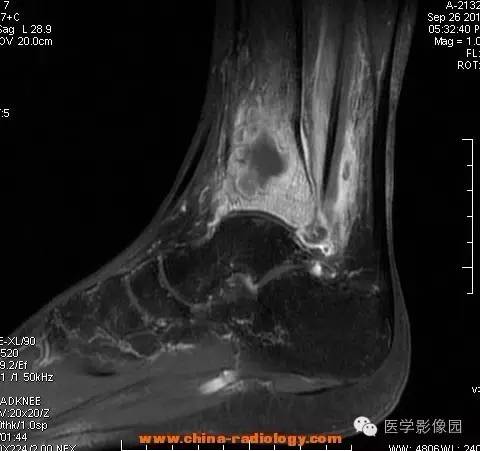

影像学表现:胫骨中下段干骺端不未规则形长T1长T2信号,T2WI见不完整环形稍低信号影,T2脂肪抑制低信号更明显,并见胫骨下段及踝关节后外侧软组织呈弥漫稍高信号,增强明显不均匀强化,增强见低信号环内有环形强化影。

影像学表现:表现为长骨干骺端有椭圆形密度减低区,边缘有清晰的骨质硬化,病变与邻近正常骨髓腔境界清楚。MRI上T1WI呈低信号,少数呈等信号,T2WI多为混杂高信号,增强扫描可见环状强化,强化的脓肿壁薄而均匀。